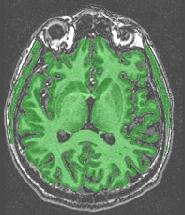

extra-cerebral structures

The mask includes anatomical structures which do not belong to the brain:

This is a failure of the erosion process supposed to break down brain connexions with the outside world (optical nerves, etc.). This failure results from a bad tuning of the erosion size during the automatic adjustment loop. Usually, the extra-cerebral structures are connected to cerebellum and/or temporal lobes. If only the cerebellum has this problem, you can proceed further because the cerebellum will be removed during further processing. Otherwise, try one of the variants with fixed erosion size, trying to keep this size as small as possible. In case of success, check that the erosion did not become too large. In such a case, some gyri may have been deleted. Then, you will have to choose the best trade-off.